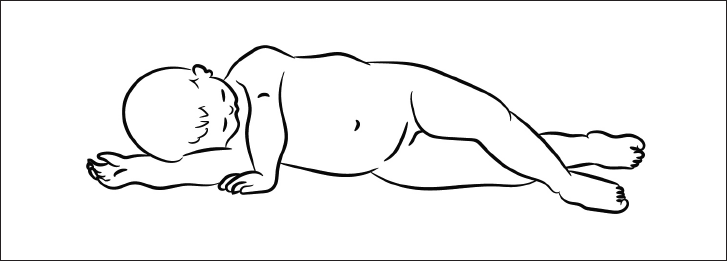

1. Рефлекс переворачивания

Когда ребенок долго лежит на спине, он пытается перевернуться. Его побуждает к этому рефлекс переворачивания (рис. 17).

Он состоит из координации нескольких движений: разворот ног, поворот туловища, разворот плечевого пояса и поворот головы. В дальнейшем эта последовательность движений реализуется при формировании спиралевидной МФЦ. Она начинается от боковых мышц стопы и заканчивается на руке и шее.

Патобиомеханика. Если по какой-либо причине выключаются мышцы, составляющие одну из цепей, возникает деформация статики в виде бокового смещения таза, мышечно-тонического сколиоза, наклона головы в сторону. Поэтому, чтобы убрать одну из найденных деформаций, необходимо восстановить полноценность МФЦ.

Рис. 17. Рефлекс переворачивания.